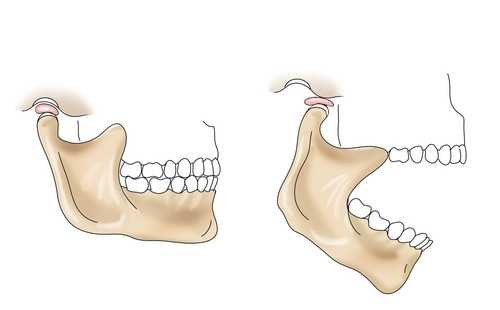

Метастаз мыщелка нижней челюсти, имитировавший острую дисфункцию височно-нижнечелюстного сустава

Метастазы раковых опухолей в нижнечелюстной мыщелок встречаются редко. В данной статье описан случай единичного метастаза в мыщелок нижней челюсти, имитировавший острую дисфункцию височно-нижнечелюстного сустава. Интраоперационная биопсия показала опухоль головки сустава, прорастающую сквозь кортикальную пластинку в подвисочную ямку, гистологическое исследование выявило крупноклеточный метастазирующий рак лёгких. Исходя из данных исследования можно сделать вывод, что пациентам, не отвечающим на стандартную терапию, или демонстрирующим отрицательную динамику, должна быть выполнена обзорная рентгенограмма зубов и челюстей; особое внимание при этом следует уделить остеолитическим процессам костной ткани, которые могут быть проявлением метастазирующей опухоли.

Впервые метастаз раковой опухоли в нижнечелюстной мыщелок был описан в 1947 году; на данный момент в литературе описано 23 подобных случая. Примерно в половине описанных случаев симптомы соответствовали симптомам дисфункции височно-нижнечелюстного сустава.

Различные виды нарушений анатомии и физиологии височно-нижнечелюстного сустава достаточно широко распространены и становятся причиной появления боли или дисфункции сустава у миллионов людей. Всех пациентов можно условно разделить на две большие группы: тех, чьё заболевание возникло на мышечном субстрате, и тех, чьё заболевание связано с патологией сустава. В обеих группах выделяют диагностические подкатегории. Суставные нарушения могут возникать в результате врождённых и приобретённых нарушений, посттравматических нарушений, анкилоза, артрита, неоплазии сустава, а также функциональной дисфункции сустава. Мышечные нарушения включают в себя миозит, миофасциальный болевой синдром, мышечный спазм, гипер- гипокинезию, мышечную контрактуру и фибромиалгию.

В данной статье описан редкий клинический случай крупноклеточного рака лёгких с единичным метастазом в мыщелок нижней челюсти, имитировавший острую дисфункцию височно-нижнечелюстного сустава.

В клинику поступила 72-летняя женщина с жалобами на усиливающуюся с течением времени боль в левом височно-нижнечелюстном суставе, ограничение подвижности нижней челюсти и патологический прикус в течение трёх предыдущих месяцев. Температура тела пациентки в пределах нормы, состояние удовлетворительное, осмотр и инструментальное обследование ротовой полости патологии не выявили.

Для вычисления индекса дисфункции по методу Helkimo была проведена двусторонняя оценка функции сустава. Индекс правого сустава оказался равен 0 (норма), левого сустава — III (серьёзная дисфункция). При пальпации сустав чувствителен, при движении в суставе проявлялся болевой синдром, наблюдалось значительное ограничение подвижности нижней челюсти до 25 мм. Мышечных спазмов не было, звуковые шумы при движении в суставе не отмечались. Подвижность в горизонтальной плоскости спереди назад снижена до 1 мм, подвижность при движении в правую сторону снижена до 2 мм, при движении в левую сторону находится в пределах нормы (9 мм). Был поставлен клинический диагноз передняя дислокация внутрисуставного диска височно-нижнечелюстного сустава.

Описанный нами случай интересен своей уникальностью: наличием метастаза крупноклеточного рака лёгких в мыщелок нижней челюсти, клинически имитировавшим переднюю дислокацию внутрисуставного диска височно-нижнечелюстного сустава.

Клинически метастаз в мыщелок нижней челюсти может проявляться болью в суставе, как в покое, так и при движении, и тризмом, что сходно с симптомами артрита сустава. Также в литературе описаны случаи неопластической нейропатии, затрагивающей область отхождения от тройничного нерва лицевой ветви.